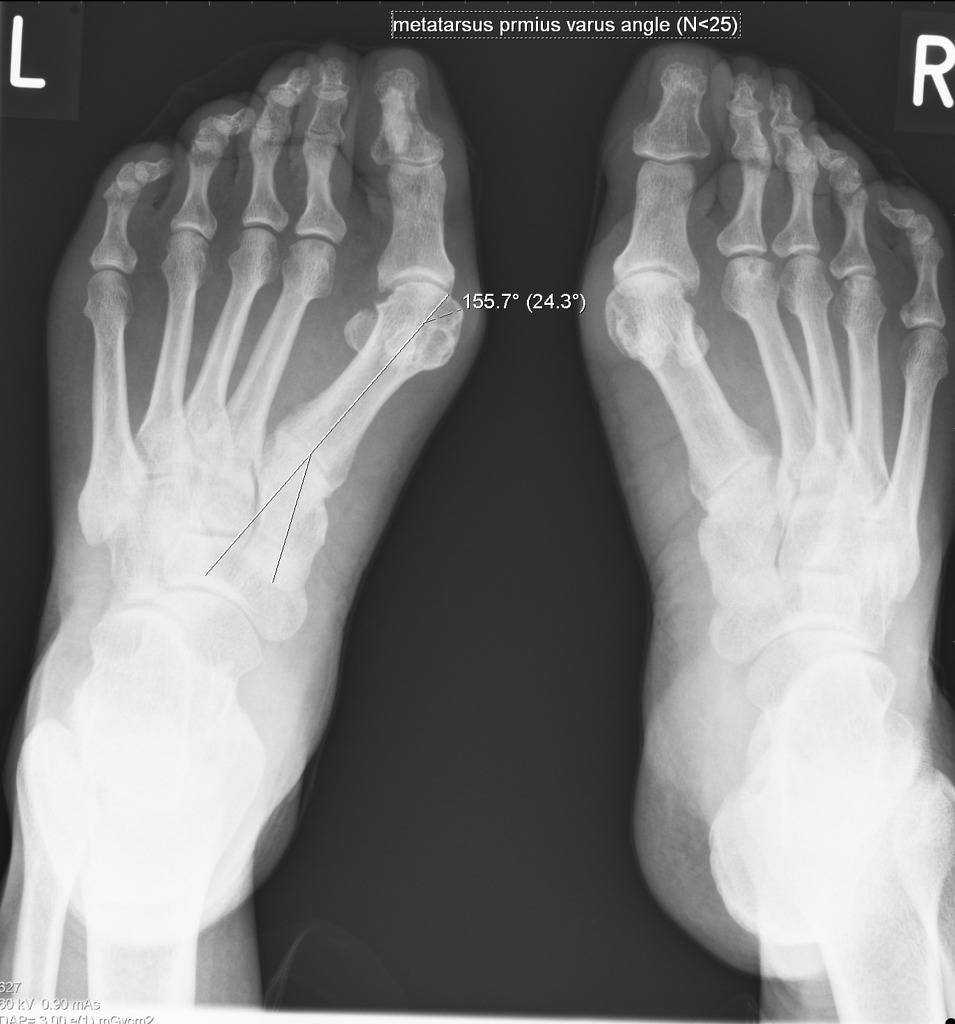

В зависимости от выраженности симптоматики, врачи выделяют три степени вальгусной деформации стопы:

- Легкая (1 стадия) – пациент жалуется на умеренный дискомфорт в области стопы, а визуально отмечается легкая отечность и покраснение тканей возле большого пальца. При осмотре специалист выявит высоту продольного свода стопы в пределах 15-20 мм, угол наклона пятки до 15 градусов и угол высоты свода до 140 градусов.

- Средняя (2 стадия) – на этой стадии появляется выпирающая косточка на боковой поверхности стопы, а пациент испытывает сильную боль при ходьбе и не может носить обувь без дискомфорта. Со стороны специалистов симптомы средней стадии вальгусной деформации следующие – высота свода до 10 мм, угол наклона пятки до 10 градусов, угол высоты свода 150-160 градусов.

- Тяжелая (3 стадия) – в этом случае пациент испытывает сильную острую боль в области стопы не только во время ходьбы, но и в состоянии покоя. Существенные деформации стопы приводят к нарушению походки, повышению нагрузки на позвоночник и перекосу всего тела пациента. Это приводит к серьезным патологиям позвоночного столба, суставов и костей. Врач при этом отметит следующие характеристики деформации стопы: высота свода 0-5 мм, угол наклона пятки 0-5 градусов, угол высоты свода 160-180 градусов.